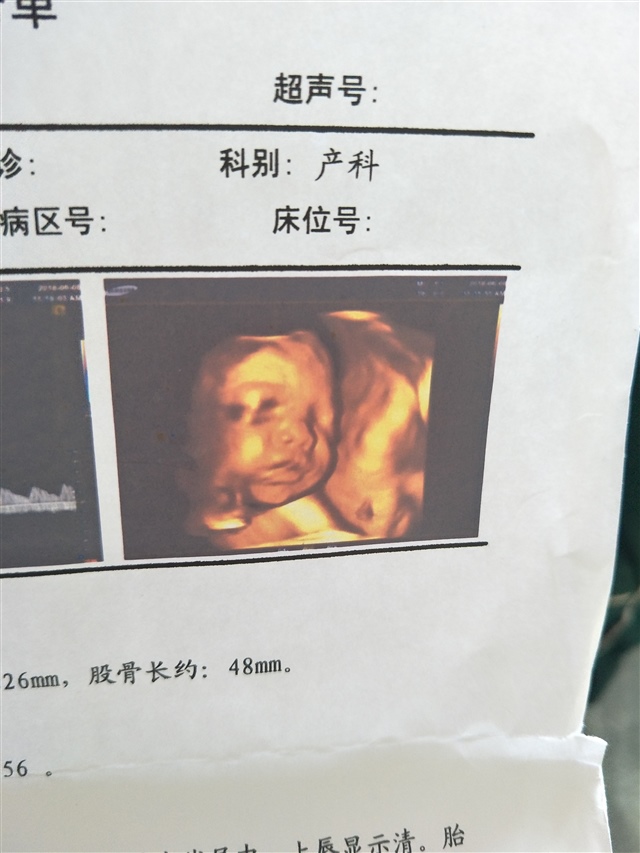

稚念[帖主]:这个是普通的四维彩超,我是27周去做的